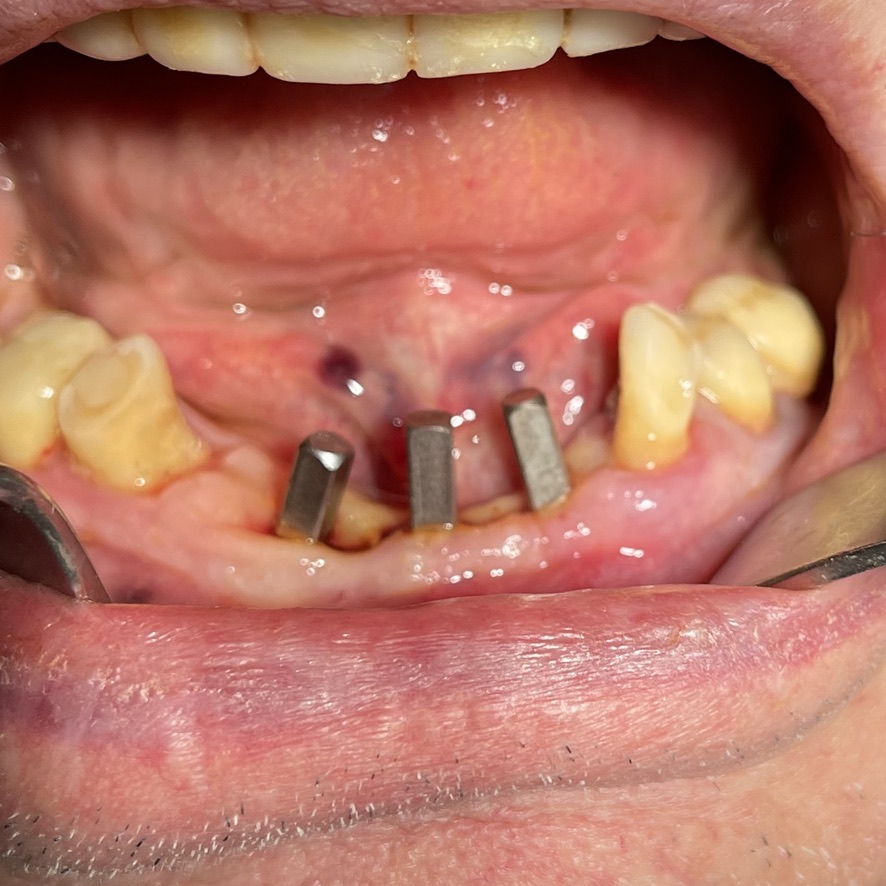

CASO CLINICO : Riabilitazione del 28/04/2021

In particolare considero notevoli i seguenti aspetti:

• 13 l’inserimento dei tre impianti non ha comportato innesti di osso o di tessuti connettivali.

• 14 Non ha reso necessari scollamenti

• 15 Non è stata necessario isolare le emergenze dei nervi alveolari inferiori

• 16 Trattandosi di osso ad elevata densità si è ricorsi alla fresa elicoidale, strumento raramente utilizzato da noi perchè non necessario e perchè ci sono zone in cui il suo utilizzo comporta rischi chirurgici per noi non accettabili. Inoltre questa fresa asporta quantità discrete di osso che preferiamo resti dove la natura lo ha messo. Interessante il fatto che il diametro della fresa è di solo 2 mm

• 17 Trattandosi di osso denso, gli impianti utilizzati avevano un diametro di soli 4 mm dopo maschiatura col corrispondente maschiatore.

• 18 Al controllo del 3/5/2021 il paziente non è gonfio e riferisce che mangia finalmente bene.

• 19 Inizio intervento implantare alle 8.45. fine intervento implantare alle 9.36.

• 20 Cementazione del provvisorio, confezionato al momento, ultimata alle 10.30. durata totale permanenza del paziente in ambulatorio1,45 ore.

Le immagini forniscono nelle didascalie ulteriori informazioni.